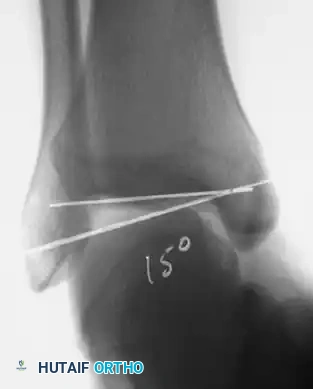

- Stress Radiography: Mechanical instability is confirmed when stress radiographs demonstrate 8 to 10 degrees of increased talar tilt in the ankle mortise compared with the contralateral normal ankle.

Associated Surgical & Radiographic Imaging